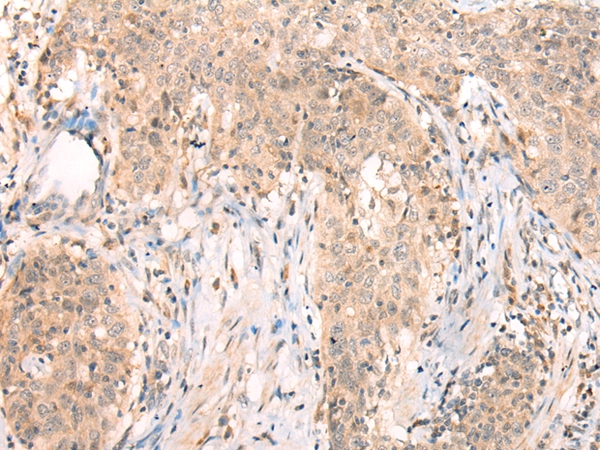

Immunohistochemical analysis of paraffin-embedded Human esophagus cancer tissue using #43286 at dilution 1/20.